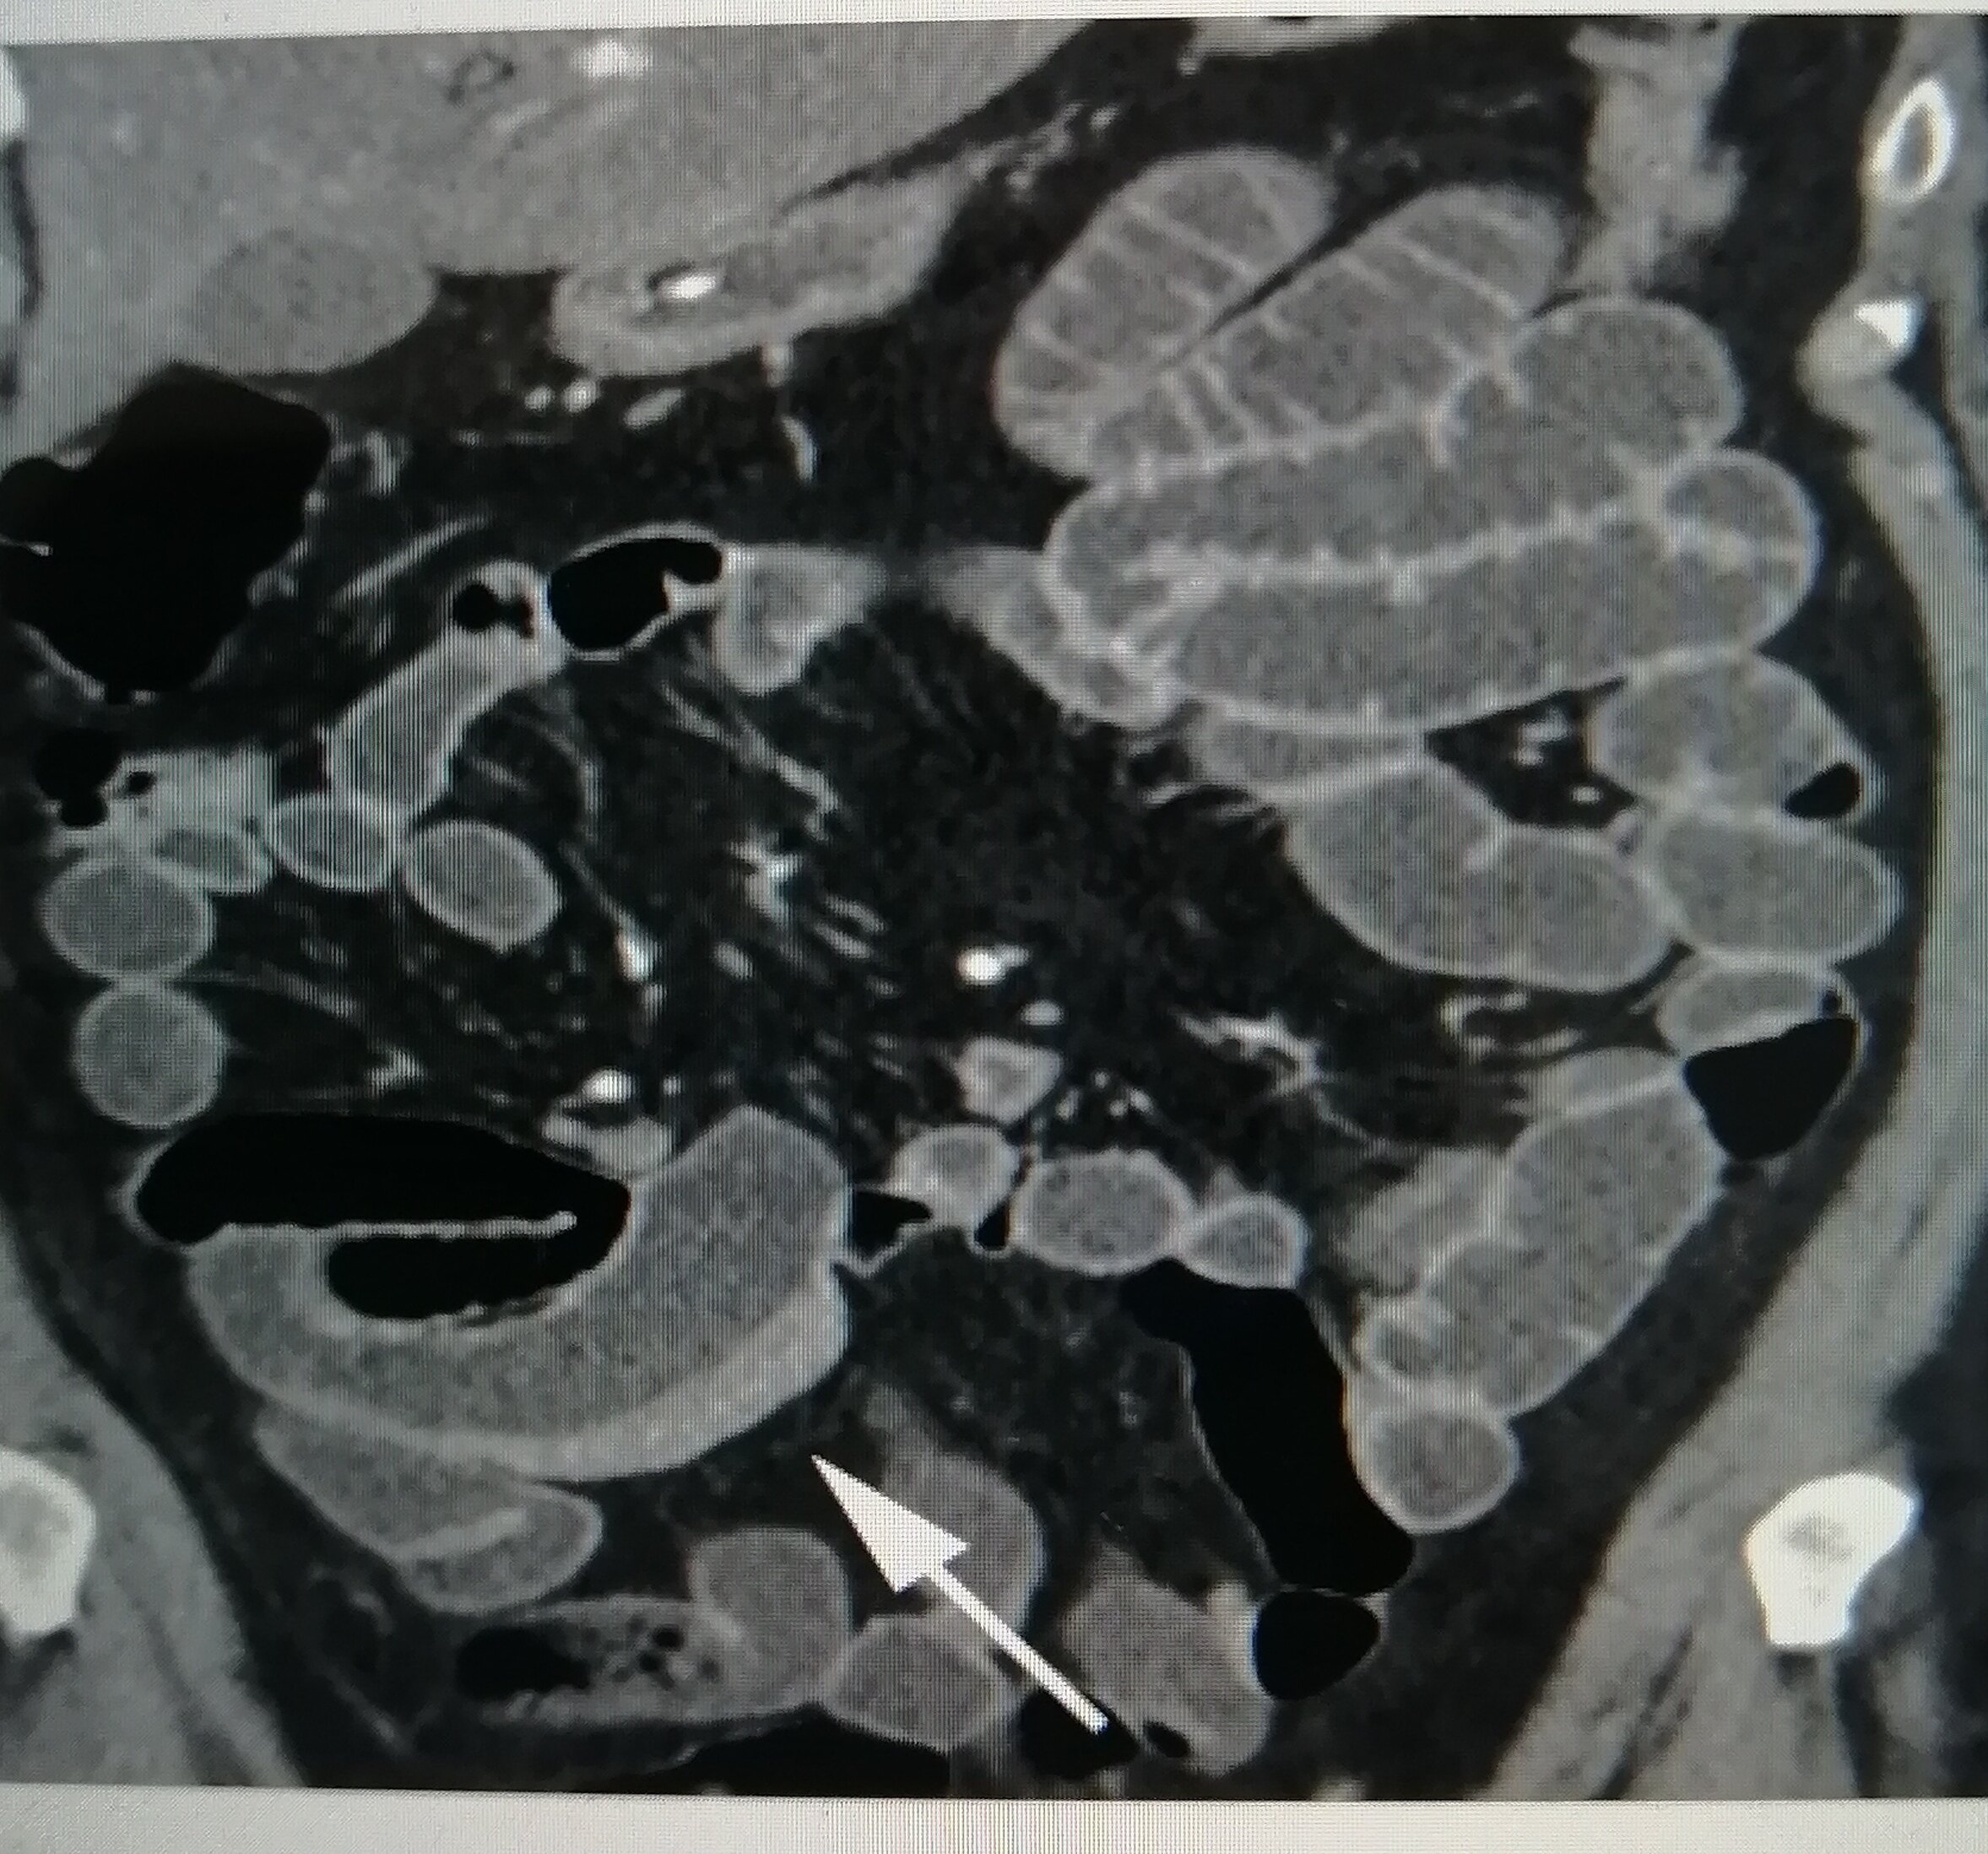

然后,医生还会让我去做一些检查,比如验血啊,做肠镜啊,看看肠子里有没有那些发炎的痕迹。有时候,还得做做CT或者MRI,看看肚子里的情况。这些检查听起来就让人紧张,但为了搞清楚到底是不是克罗恩病,也只能硬着头皮上了。